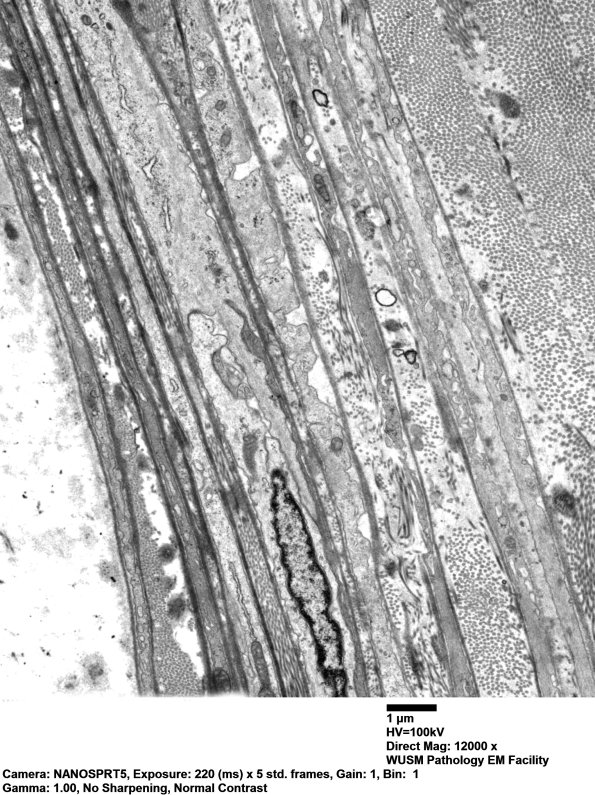

0A2 An electron microscopic image of a typical normal sural nerve perineurium. The perineurium is composed of flattened cells separated by collagen. The number of lamellae usually parallel the size of the fascicle. (electron micrographs)